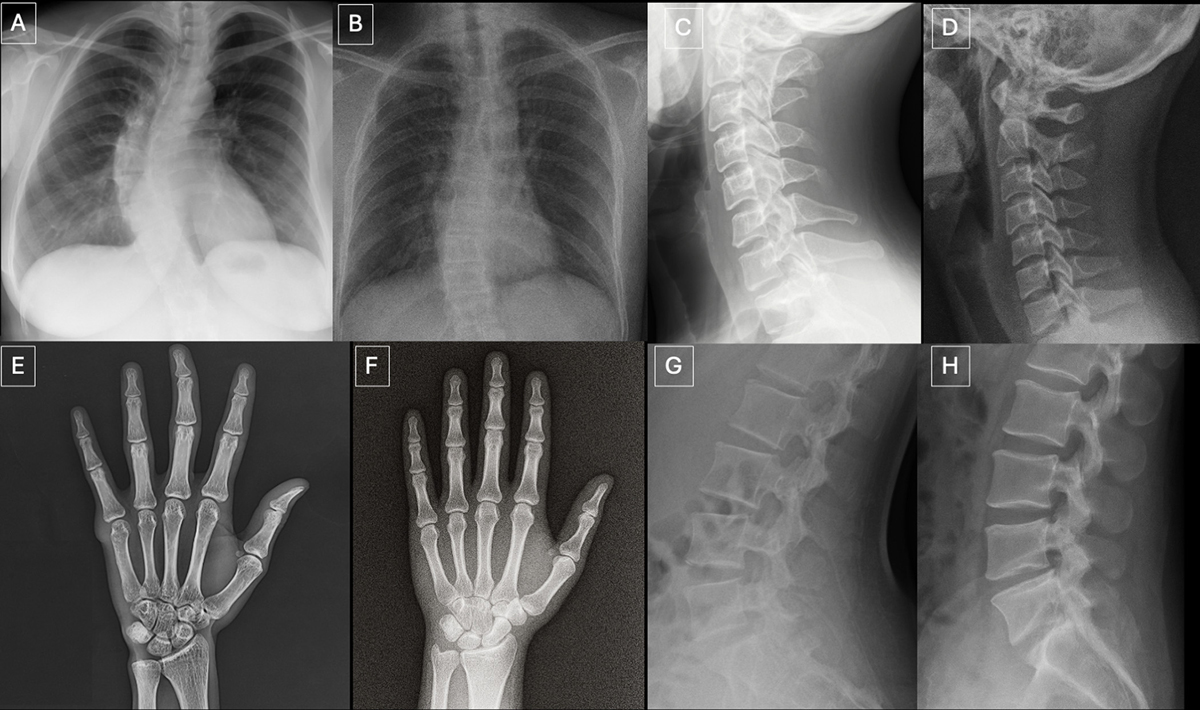

연구팀은 딥페이크 엑스레이 사진의 특징도 제시했다. 실제 엑스레이 사진과 달리 뼈가 지나치게 매끄럽고, 척추가 비정상적으로 곧으며, 폐가 과도하게 대칭적인 등 ‘지나치게 완벽한’ 형태를 보이는 경우가 많다는 것이다. 골절 역시 한쪽 면에만 국한되거나 지나치게 깨끗한 형태로 나타나는 경향이 있었다. 연구 주 저자 마운트 시나이 아이칸 의과대학 미카엘 토르드즈만 박사는 “이번 연구는 딥페이크 엑스레이 사진이 인공지능으로 생성된 사진임을 인지하고 있는 전문가조차 속일 수 있을 만큼 현실적이라는 것을 보여준다”며 “이러한 발전의 다음 단계는 CT, MRI가 될 수 있다”고 말했다.